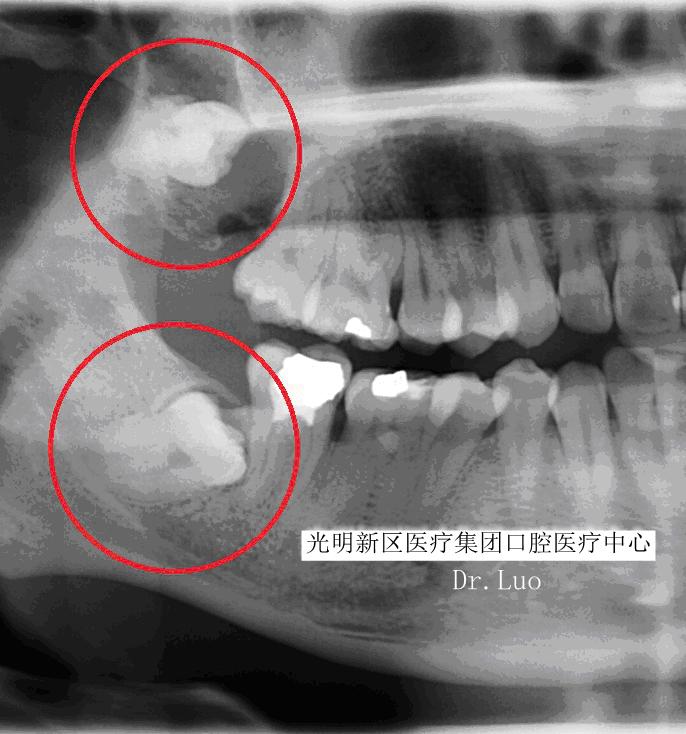

而“阻生”智齿是之那些由于邻牙、骨或软组织阻碍而只能部分萌出或完全不能萌出,且以后也不能萌出的第三磨牙。

那么阻生智齿有什么危害呢?

1)上、下后牙反复肿痛:

有时候智齿出现了,却依旧发生局部肿痛,严重的时候甚至可以让整个半侧脸颊肿的像个水球,这种情况就是冠周炎,是指整个牙冠周围发生了炎症。

由于智齿(特别是下颌的)周围特殊的解剖结构,炎症常常会侵袭到周围间隙组织,造成如最常见的半侧面颊的肿胀。如果炎症侵袭的下颌后部的间隙组织,造成喉头水肿、气道压迫,那么威胁生命不是危言耸听。

2)龋坏:

由于智齿本身生长位置就比较靠后,清洁起来有一定难度,所以蛀牙情况很普遍,有些智齿不甘寂寞自己蛀牙,还会把前牙累及。

3)塞牙:

很多时候智齿的生长会和前牙形成一个夹角,形成一个空间。食物往往会嵌塞其中,让您感到不适。长期的食物嵌塞不光会造成牙龈的红肿、退缩,甚至可以是牙槽骨吸收,形成恶性循环,加重食物嵌塞。

4)根、骨吸收:

由于智齿生长持续的压力压迫,造成邻近牙齿、骨质的吸收。可导致邻牙不适、疼痛甚至松动脱落。

5)牙源性囊肿、肿瘤:

长期的炎症、压迫周围组织可能导致颌骨囊肿、牙源性肿瘤的产生。不仅可能造成邻牙的松动脱落,还可能引起下颌神经的损伤、颌骨的病理性骨折,甚至有肿瘤后癌变的可能。

6)拥挤:

智齿生长带来的持续性挤压可能是造成您牙齿不齐的重大原因。

7)下颌关节紊乱:

由于智齿临近咀嚼肌群,所以它有点风吹草动直接会影响到咀嚼肌。肌肉收到压迫而痉挛,最重可造成完全张不开嘴,又称“牙关紧闭”。

阻生智齿的罪过如此之多,引起的疾病如此棘手,所以面对阻生智齿,面对这个不定时的*弹炸**我们必须毫不手软,坚决予以铲除——尽快拔除。